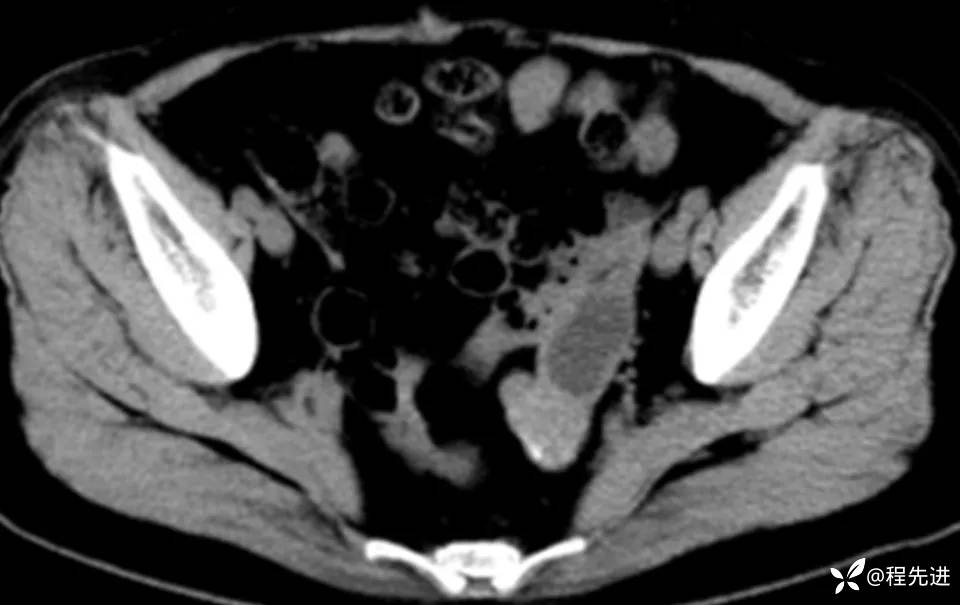

CT平扫+增强:

img